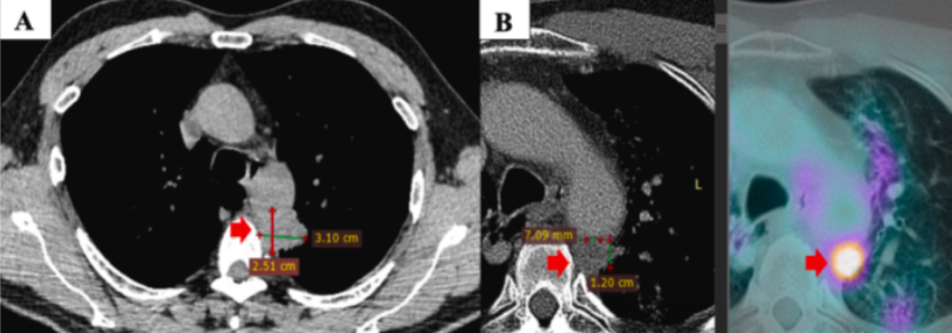

图:患者接受3个周期的一线干预方案:卡铂+紫杉醇双药化疗,并在第三个周期联合放疗。干预后PET/CT显示病灶缩小到12×7mm(图B),取得部分缓解,肿瘤标志物回复正常,并改善了一些临床症状。

图:PET/CT复查显示局部进展,原发病灶大小增大为28×29mm,SUVmax值为11.2,并侵袭到纵膈胸膜和主动脉。此外,左侧锁骨上淋巴结新发转移灶,9×6mm(图B)